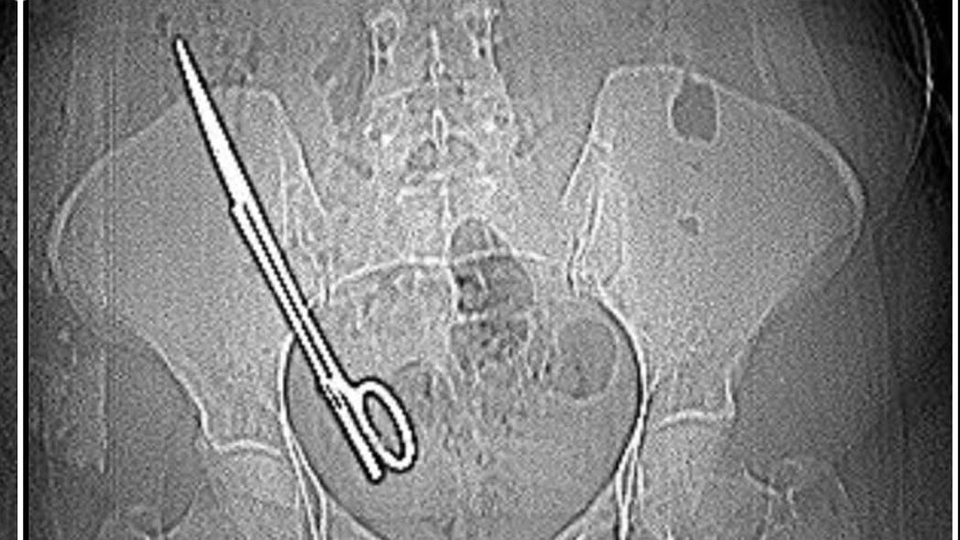

İddiaya göre; Koray Ş., 7 yıl önceki ameliyattan dolayı bir komplikasyon oluştuğunu ve acilen ameliyat etmesi gerektiğini söyledi. Doktorun tavırlarından şüphelenen Fatma Kala, ameliyat olmayı reddedip KSÜ Sağlık Uygulama ve Araştırma Hastanesi'ne gitti. Burada yapılan tetkiklerde Kala’nın karnında 16 santimetre uzunluğunda makas olduğu tespit edildi. Ameliyatla karnındaki makas çıkarılıp sağlığına kavuşan Fatma Kala, hastaneden çıktıktan sonra avukatı aracılığıyla 7 yıl önce ameliyatı gerçekleştiren doktor Koray Ş. hakkında Kahramanmaraş Cumhuriyet Başsavcılığı’na suç duyurusunda bulundu.

Teknisyen bana 'Bu şekilde seni MR'a alamam, çok tehlikeli. Acilen ameliyat olduğun doktoru bul' dedi. Doktorumuz bizi hemen röntgene aldı. Röntgende bir yabancı cisim görmüş ama bize söylemedi, ‘Daha önceki ameliyatından dolayı bir komplikasyon oluşmuş. Seni ameliyat edip dedi o komplikasyonu ortadan kaldırmam gerekiyor’ dedi. Biz doktorun telaşlı tavrından şüphelendik. Eşimle birlikte tıp fakültesine gittik. Oradaki acil doktorlarına başımızdan geçen olayı anlattık. Onlar beni röntgene soktu. Oradan ilaçlı tomografiye girince daha önceki ameliyatımda bırakılan makas orada görüldü. Genel cerrahi bölümünde bu makas çıkarıldı'' diye konuştu.